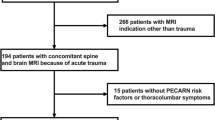

Identification of study groups and clinical data acquisition

The prospectively maintained electronic databases of our hospital were queried for all patients younger than or at age 18 years who were admitted for mild TBI (GCS 13-15) (January 2009 to July 2016). Patients who received cranial MRI as initial imaging modality as part of their emergency assessment were included in the study. Their charts were reviewed retrospectively for age, sex, type of injury, clinical features, further clinical course, and duration of hospital stay. Headache and amnesia were evaluated in children older than 4 years of age. Children with suspected non-accidental injury were excluded.